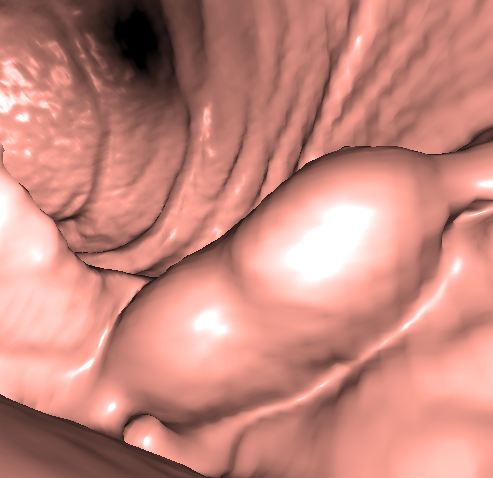

In recognition of awareness for these diseases, I want to highlight several specialized radiological methods offered at UCSF. These methods are geared toward non-invasive imaging of the stomach and esophagus. These imaging procedures utilize oral effervescent granules, which naturally form a small amount of carbon dioxide gas in the stomach to provide gaseous distension of the stomach as a means to obtain a detailed look at the stomach wall at CT and fluoroscopy. From CT image sets, three-dimensional reformations are generated to identify or stage tumors. These reformations allow us to take a more detailed look beyond the bowel mucosa to search for inflammation or lymph node enlargements in nearby areas of the abdomen.